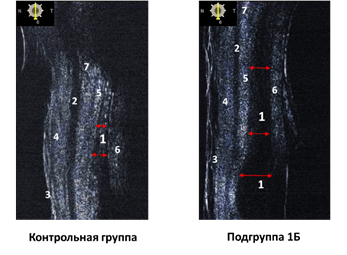

У 18 пациентов с жировой дистрофией (1Б) при УБМ визуализирована утолщенная мышца Мюллера (0,36 ± 0,045 мм) по сравнению с нормальным веком (0,23 ± 0,027мм), кроме этого, апоневроз леватора (0,167 ± 0,035мм) имел незначительное истончение (табл. 2, рис. 5). Макроскопическая интраоперационная ревизия и гистологическое исследование соответствовали данным УЗИ.

Рис. 5. Обозначения: 1 – мышцы Мюллера; 2 – круговая мышца глаза; 3 – кожа; 4 – слой соединительной ткани; 5 – апоневроз леватора; 6 – склера; 7 – тарзоорбитальная фасция

Источник: составлено авторами по результатам данного исследования.